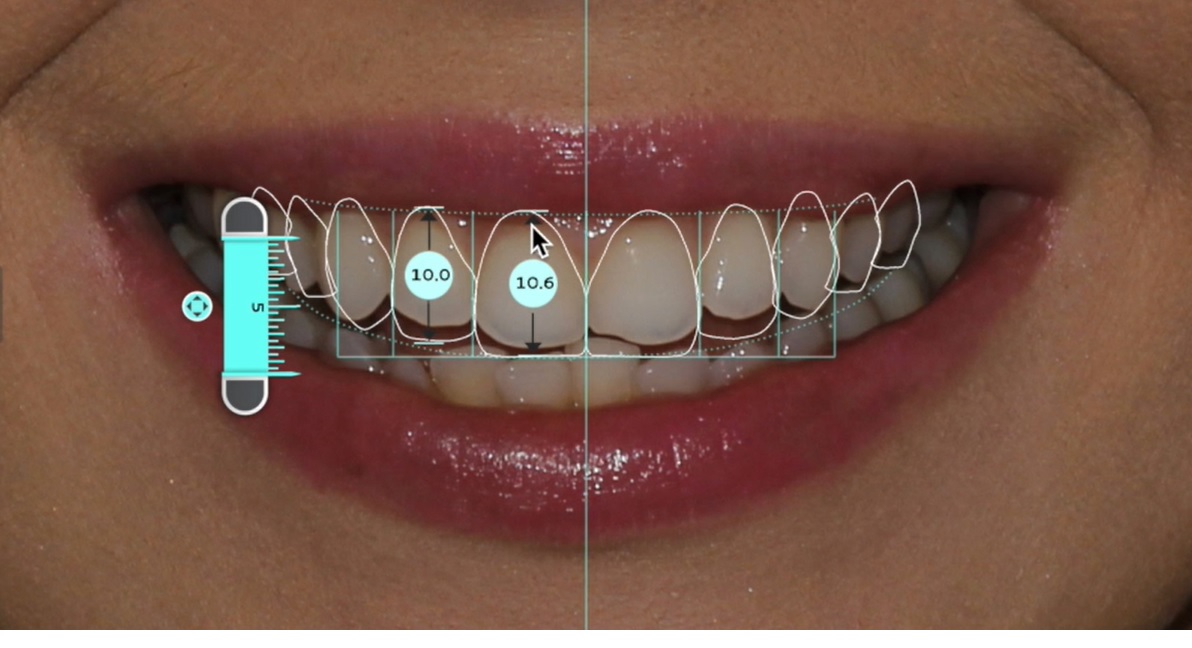

Belirlenen yeni diş yapısı ve dental oranlara göre gülüş tasarım yazılımı, planlanan tedavinin bitmiş halinin sanal görüntüsünü oluşturur. Bu görüntü üzerinde, hastanın da istek ve düşünceleri dikkate alınarak gerekli düzeltmeler yapılır.

Son hali verilen dijital gülüş tasarımı üzerinde dijital ölçümler yapılarak veya doğrudan Cad-Cam cihazlar kullanılarak dijital planlama , Mock-up adı verilen reel tasarıma dönüştürülür. Daha sonra, Mock-up tasarım, ağıza aktarılarak geçici dişler üretilir. Bu aşamada , yüz-dudak ve alt-üst dişlerin birbirleriyle uyumları ile diş renk ve boyutları, dişeti konturları detaylı olarak tekrar değerlendirilir. Bu değerlendirmeler sonrasında Mock-up üzerinde gerekli son düzenlemeler yapılıp protetik işlemlere geçilir. Bu iş akışı neticesinde elde edilen estetik sonuç, dijital tasarım ve Mock-up çalışması ile oldukça uyumludur.

Dijital Gülüş Tasarımı, pekçok farklı diş tipi ve renginin hastaya daha uygulanmadan bilgisayar ortamında denenmesi , hastanın görüşünün alınması , sonuç olarak da, hekimin ve hastanın beğenip onay verdiği tedavinin gerçekleştirilmesine imkan verir.